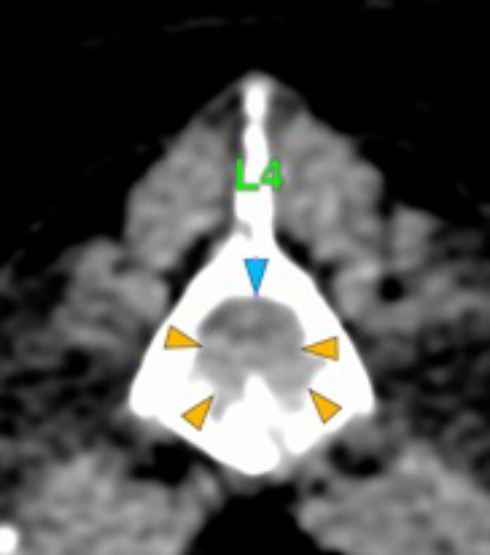

The osteolytic lesions have soft tissue attenuation that shows moderate and slightly heterogeneous post-contrast enhancement. In some of the vertebrae, the lesions cause lysis of the cortex and extend into the vertebral canal (orange arrows) causing variable degree of compression of the spinal cord and cauda equina (blue arrows). At the level of the vertebral bodies of T7, T8, T9 and T12 the lesions extend into the ventral and central aspect of the vertebral canal causing a mild compression of the spinal cord. At the level of T13, L1, L4 and L5 the lesions extend into the ventral and central aspect of the vertebral canal, causing moderate compression of the spinal cord. At the vertebral body of L6 the lesion extends into the ventral and central aspect of the vertebral canal, at the mid-aspect of L6, occupying approx. 90% of the diameter of the vertebral canal causing a severe compression of the cauda equina. At the level of L7, the lesion extends into the ventral and both lateral aspects of the vertebral canal, causing severe compression of the cauda equina.